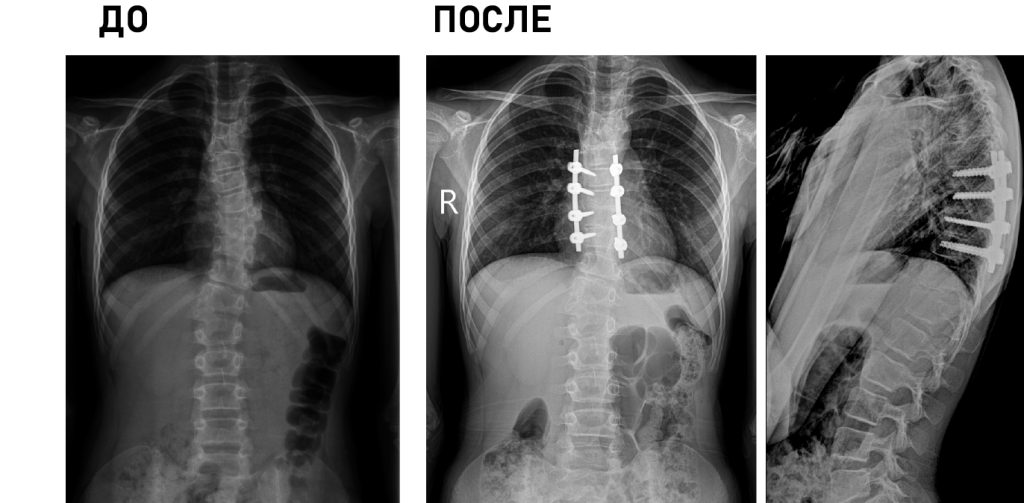

Технические возможности: технологии малоинвазивной (MIS) и реконструктивной хирургии, костнопластические материалы и инструментальная фиксация, современное силовое и ультразвуковое операционное оборудование, навигация, нейромониторинг.